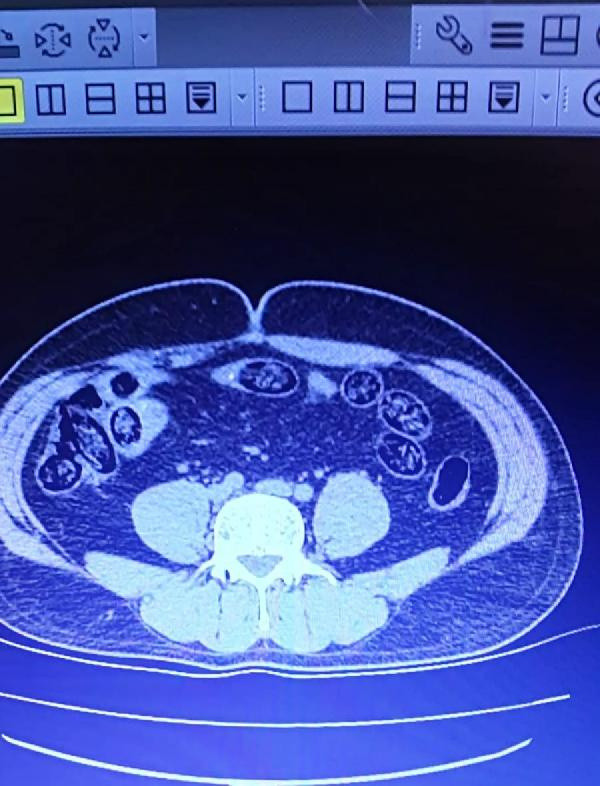

VAN Ferit Melen Havalimanı'nda 2 İran uyruklu kişi, üst araması sonrası iç muayene için hastaneye sevk edildi. 2 kişinin midesinde, 103 kapsül halinde 920 gram metamfetamin tespit edildi.

Abone olİl Emniyet Müdürlüğü Narkotik Suçlarla Mücadele Şubesi ekipleri, Van'dan İzmir'e gitmek için Ferit Melen Havalimanı'na gelen İran uyruklu 2 kişiyi şüphe üzerine durdurdu. Üzerlerinde arama yapılan ve uçağa binmeleri engellenen 2 şüpheli, iç beden muayene yapılması için hastaneye sevk edildi. Muayenede şüphelilerin midelerinde, 103 kapsül halinde 920 gram metamfetamin tespit edildi. Gözaltına alınan 2 İran uyruklu, sevk edildiği adliyede çıkarıldığı mahkemece tutuklandı.